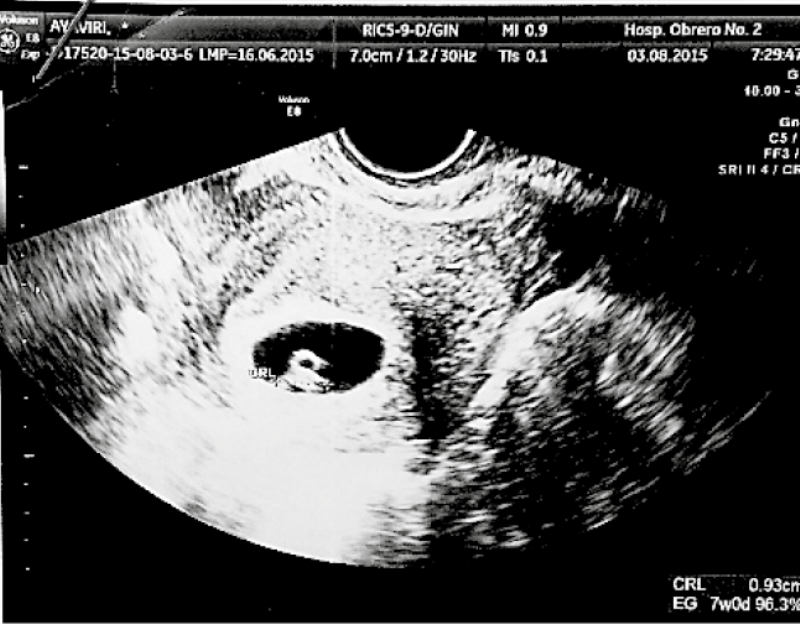

The pathological study revealed a swollen salpingeal wall, with oedema and congestion and chorionic villi, compatible with tubal ectopic pregnancy. Postoperative evolution was favourable, and a transvaginal ultrasonography was performed which revealed a vital intrauterine embryo ( Figure 3). The patient was discharged two days after the operation, receiving micronised natural progesterone 400 mg vaginally every day.